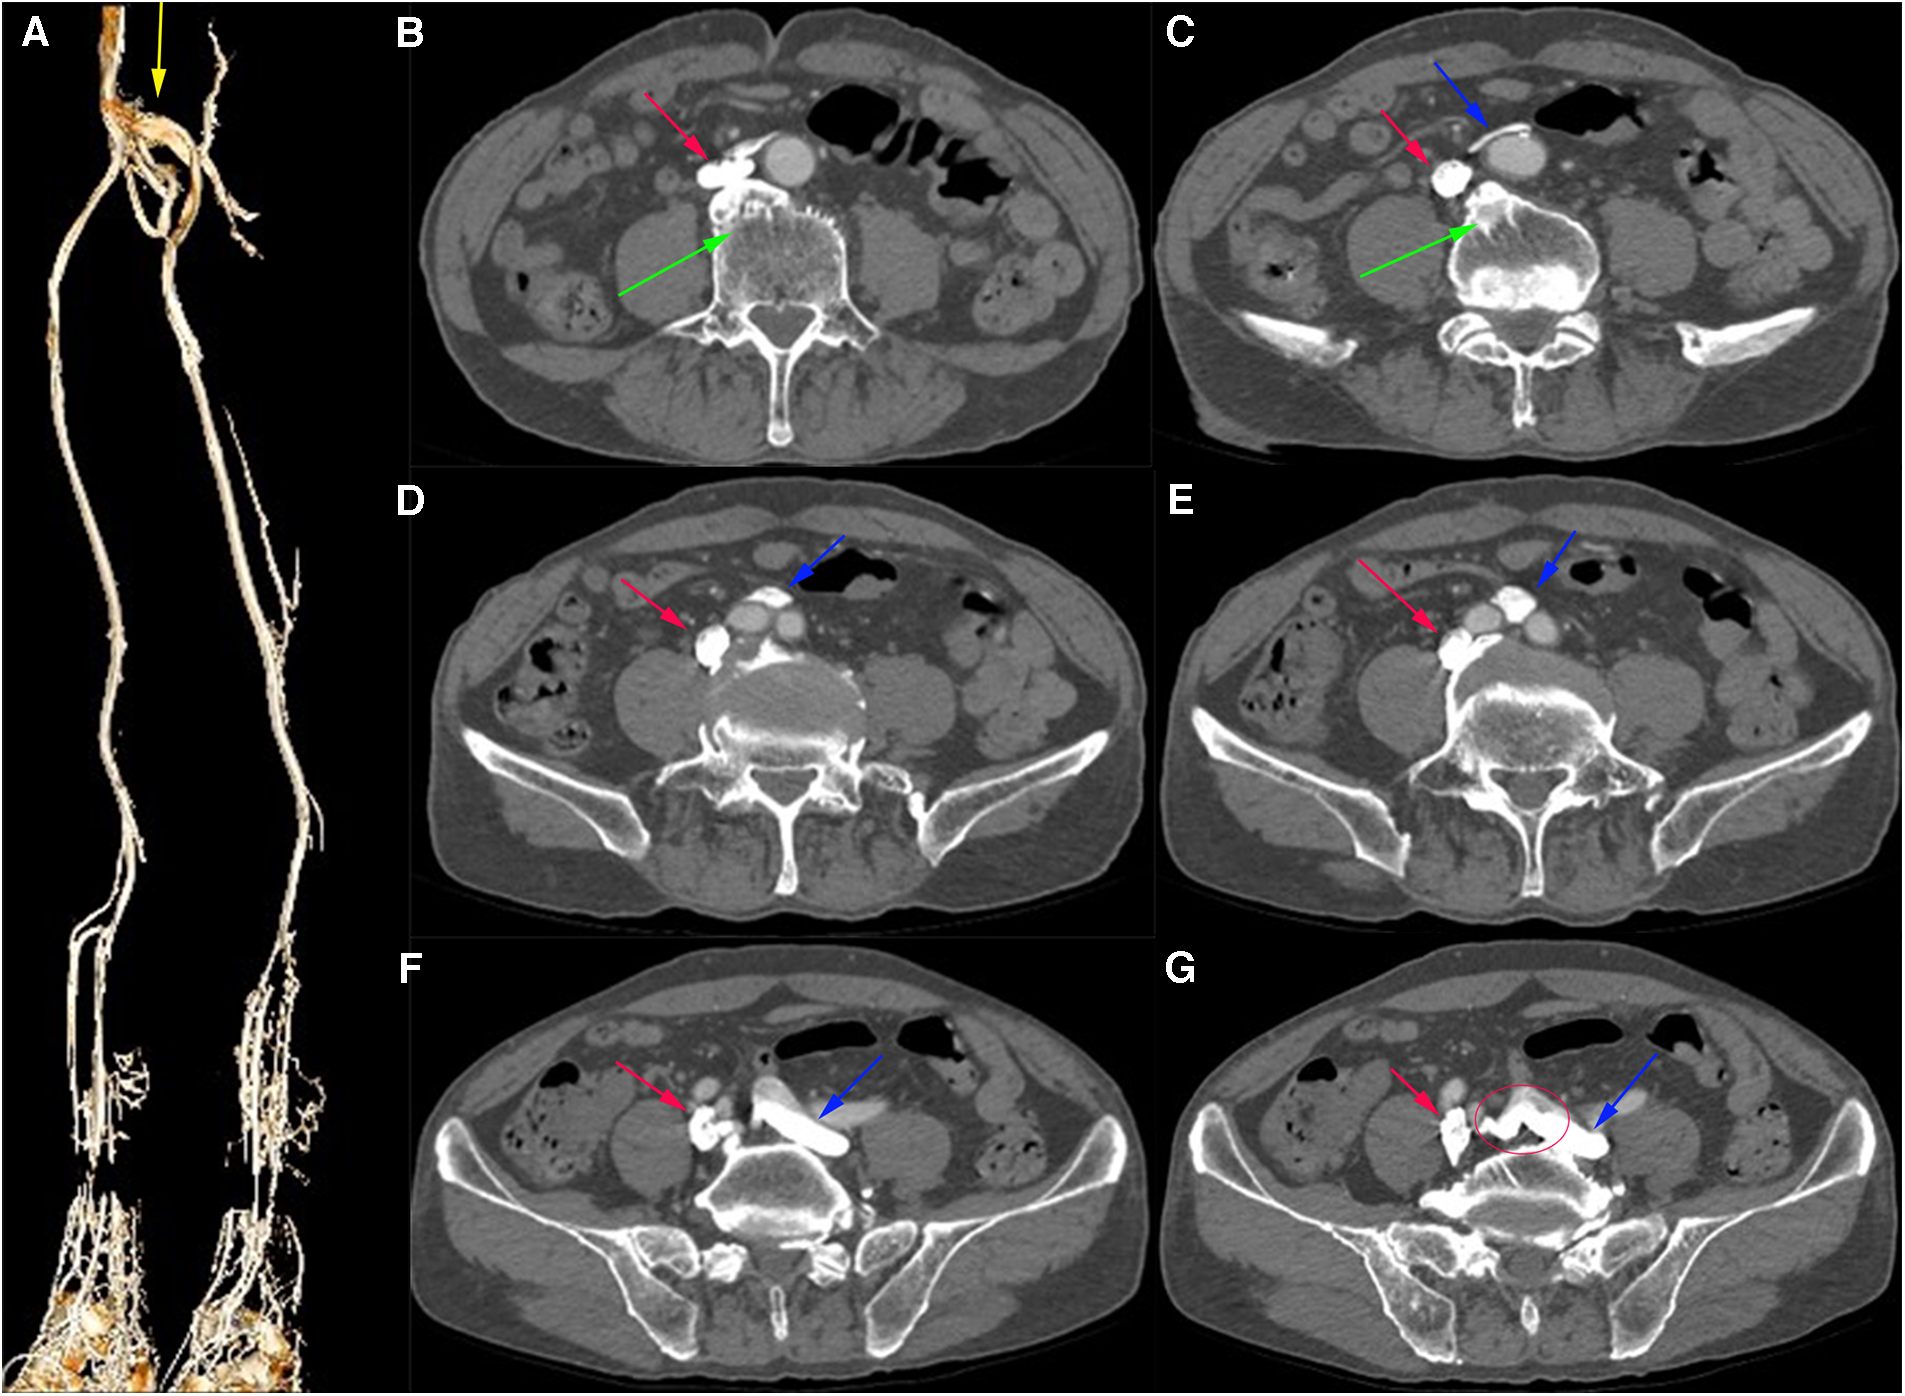

Computed tomography venography (CTV) revealed bilateral lower limb iliac vein lumen stenosis with paravalvular formation around and in front of the sacrum (Figure 2). Distorted and thickened vascular shadows were seen in the bilateral calf muscle spaces, especially on the left side. Then, CTV of IVC suggested that the left common iliac vein traveled cranially and crossed the bifurcation of the common iliac artery, and continued cephalad as a ventral vessel, while the right common iliac vein extended cephalad as a dorsal vessel. The dorsal vessel was narrowed at the level of 4th lumbar vertebrae, by the compression of the hyperplastic bone and the osteophyte (Figure 3). Both vessels run parallel to the abdominal aorta and converged on the right side of the abdominal aorta, at a level where bilateral renal veins converge 12.5 mm pedal to the IVC. The suprarenal segment, renal segment and bilateral renal veins of the IVC are normal.

Figure 2

(A) Virtual Reality (VR) image of the patient's pre-intervention CTV of lower limb, with anastomosing branches seen between the iliac veins bilaterally. (B–G) Axial venous phase image, with osteophytes seen (green arrows) and the left common iliac vein (blue arrow) bypassing the abdominal aorta ventrally and traveling dorsally from between the right and left common iliac arteries, with anastomosing branches seen between the common iliac veins.